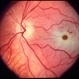

- central retinal artery occlusion, cherry red spot

- Left eye OCT of a 75 year old male with central retinal artery occlusion showing altered foveal contour with loss of differentiation of layers with thickening.